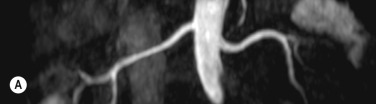

Imaging of the renal arteries for suspected renal artery stenosis can be easily performed with CTA and MRA, and the decision to use one of these modalities over the other usually depends on individual preference and experience. Renal artery stenosis is a cause of hypertension and can be caused by either atherosclerosis (which almost always affects the ostium) and fibromuscular dysplasia (FMD), which affects the vessel beyond its proximal part. The main renal arteries are medium-sized arteries that arise from the upper abdominal aorta around L1, in the vicinity of the coeliac and superior mesenteric artery (SMA) origins. The arteries can be single or multiple, and if multiple there is usually a dominant artery. Visualisation of the origin is easily performed with CTA or MRA, but challenges remain for evaluating the more distal artery (and therefore exclusion of FMD) owing to progressive decrease in artery size with distance from its origin and motion of the artery, even during perfect breath-holding owing to substantial excursion of the artery during the cardiac cycle. Secondary signs such as diminished renal perfusion and reduced kidney size are equally evaluated on CTA and MRA, although MRA offers benefit in allowing measurement of blood flow by phase-contrast techniques. Estimation of renal perfusion can also be performed directly by MR using either a contrast bolus or by arterial spin labelling ( Fig. 77.6 ).

Fig. 77.6, Patient With Hypertension Undergoing Renal Magnetic Resonance Angiography (MRA) for Suspected Renal Artery Stenosis.